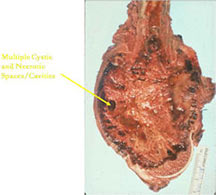

- Telangiectatic osteosarcomas have a variable gross appearance

- They may appear as a large blood clot filling a single large cystic cavity; hemorrhagic and necrotic mass; or a multicystic fluid-filled lesion

- Thin septae exist between the cystic cavities that harbor malignant appearing spindle cells producing scant osteoid

- Fleshy and sclerotic tissue typical of a conventional osteosarcoma is not seen

- Its gross appearance can mimic an aneurysmal bone cyst

- Mixture of large cystic and spongy areas